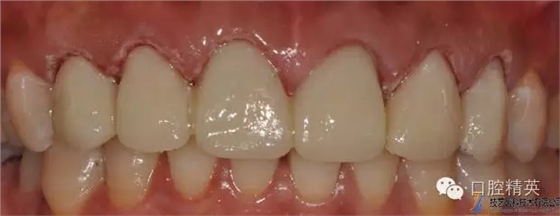

修復(fù)體完成口內(nèi)照片

640.webp (20).jpg

640.webp (21).jpg